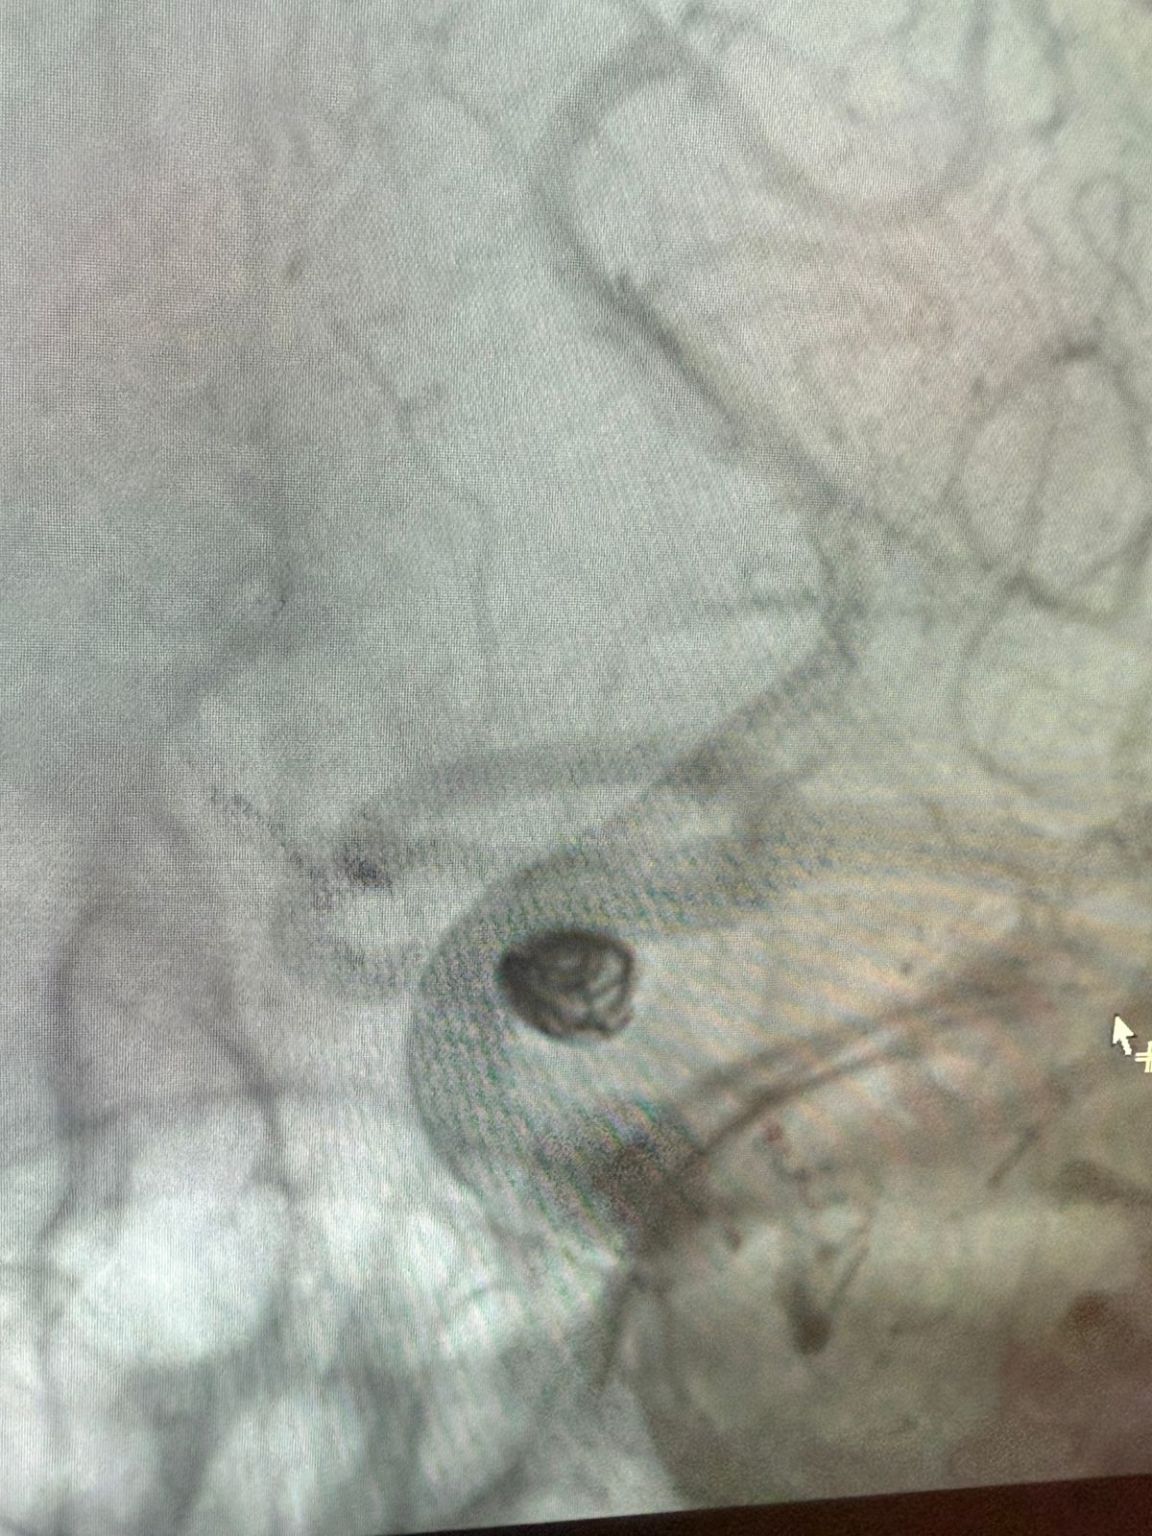

Temos o prazer de compartilhar um recente procedimento bem sucedido na Clínica Alma Mater, Medellín, realizado pelo Dr. Jorge Mutis.

O tratamento utilizou a Nuva®Desvio de fluxo (TJED-D 5.0-14), Perdenser®Bobina 3D, e Frepass®Microcateter (TJMC18 Plus) para aneurisma da artéria comunicante posterior.